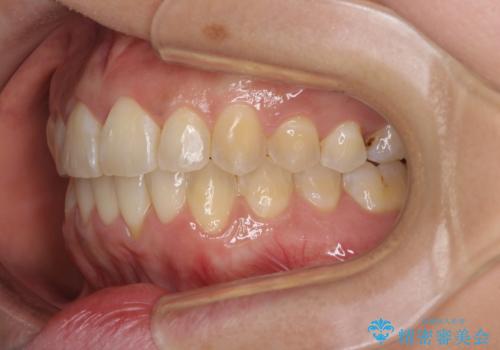

インビザラインによる狭窄歯列の拡大矯正

- 前歯のデコボコを治したいとのことで来院された患者様です。

上下顎ともに歯列全体の後方移動と側方拡大、IPR(歯と歯の間を削る)によってデコボコが解消するように設計し、インビザラインにより治療を行うこととしました。

後方移動に際し、上下の親知らずは4本とも抜歯することとしました。